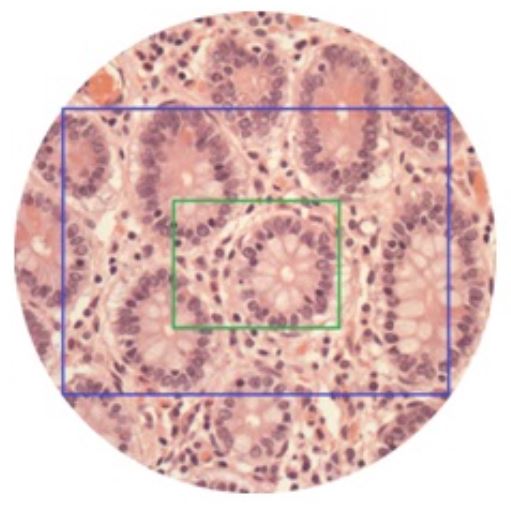

Mouse brain section confocal performance: scan a complete slice of mouse brain section with a size of 73,3mm2 with four channels and a 13 step Z-stack in 1,5 hours.

•60 μm thick section of an entire mouse brain sample is stained with 4 colors (3 antibodies and DAPI) and has been scanned by TissueFAXS Confocal at 20x magnification factor. 1400 images per each confocal plane and a total of 29400 images for 21 layers z-stack.

•Courtesy of TissueGnostics: acquisitions by courtesy of Janelia Farm Research Campus, Howard Hughes Medical Institute, Virginia, USA

•Note: TissueFAXS Confocal Plus SL integrates X-Light V2 scanner into the system